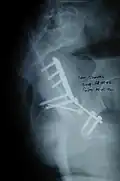

The final management depends on the size of the fragment(s), stability and congruence of the joint. In some cases traction for six to eight weeks may be the only treatment required; however, surgical fixation using screw(s) and plate(s) may be required if the injury is more complex. The latter treatment will be called for if bone fragments do not fall into place, or if they are found in the joint, or if the joint itself is unstable.

Posterior wall fracture fixed with screws and plate

Posterior wall fracture fixed with screws and plate -